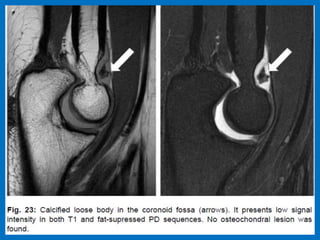

Pseudo-loose body.

Osteochondritis dissecans of the capitulum.

The T2W-fatsat image shows marrow edema and may be there is a subchondral fracture.

Obviously someone told him to keep throwing, because he came back three years later at age 17

and you can see what can happen when they push too hard in getting these kids to become a

professional. The T1W-image shows fragmentation (yellow arrow) with a loose body (red arrow).